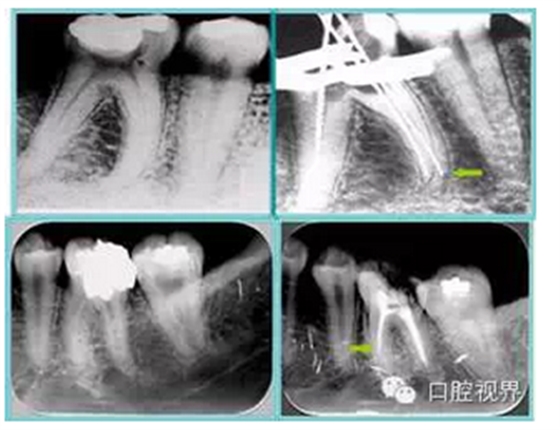

6. 術后 X 線片

術后 X 線片用來評定根管充填 長度、致密度(管壁清晰、側枝)等指標。

左圖為根管充填術后 X 線片。圖中可見,根管充填較好。右下圖有白色小點,為側方加壓導致糊劑擠出所致,表明根管充填比較致密。

致密、恰到好處的充填可去除干凈根管里感染灶,機體逐漸恢復。

多根牙時候需進行偏移投照,正位投照無法說明具體哪根牙根管充填效果。